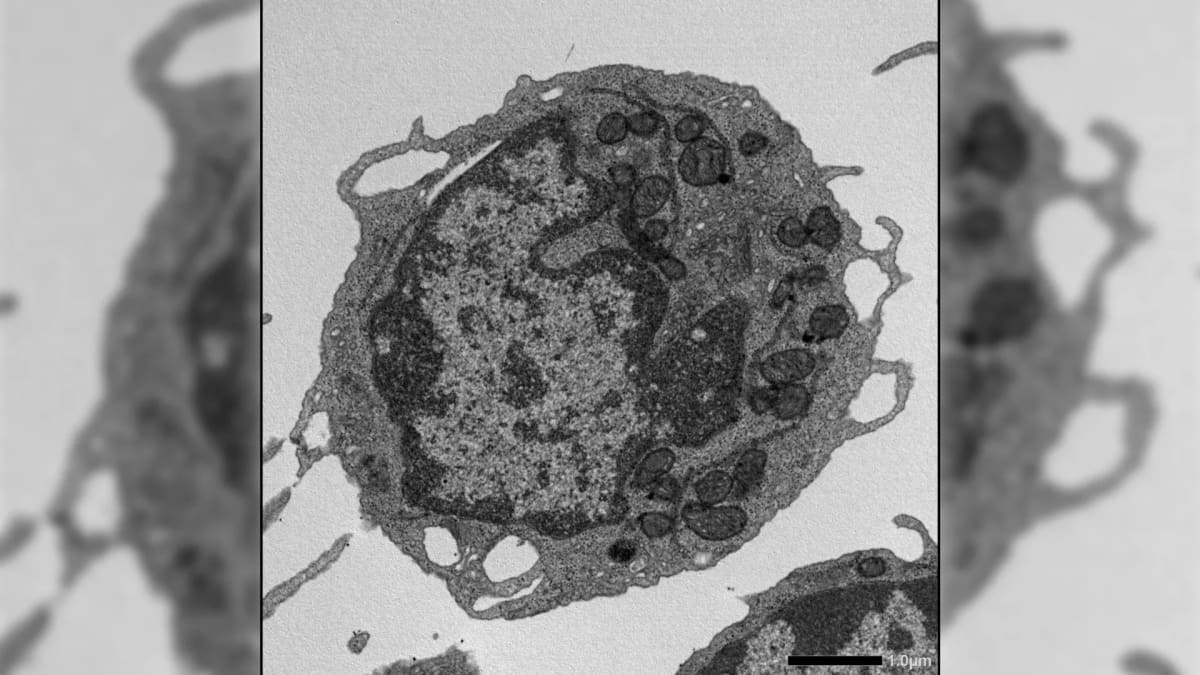

Using advanced imaging and genetic techniques, the researchers watched MLKL travel to the mitochondria, the tiny structures that power our cells. Once there, it damaged the energy production system, causing the exact problems we see in aging: weaker cells, imbalanced immune systems, and less ability to bounce back from stress.